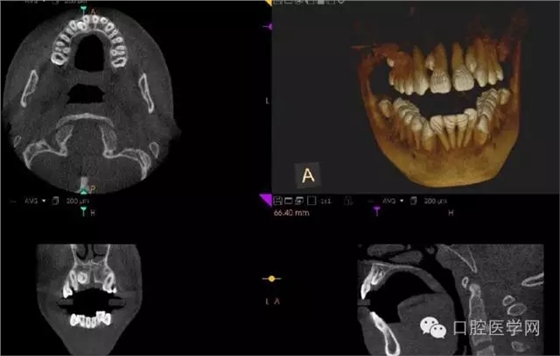

4.阻生牙

最常見于下頜第三磨牙

X線表現(xiàn):確定阻生牙的位置;確定阻生方向;牙根數(shù)目和形態(tài);阻生牙有無齲齒和根尖情況;與第二磨牙的關(guān)系;與下頜管的距離和磨牙后間隙的大小。